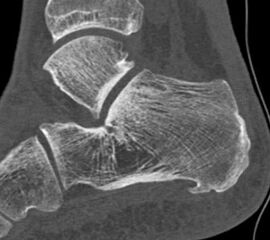

Abb. 9a–d: chron. Plantarfasziitis mit plantarem Fersensporn und Irritation Baxternerv plantar lateral

Kasuistik: 28-jähriger Patient, Profisportler.

Abb. 9a: Plantarer Fersensporn und Plantarfasziitis im MRT prä-op.

Abb. 9b: Plantarer Fersensporn im CT prä-op.

Abb. 9c: Lateraler Zugangsweg bei atypisch weit nach plantar lateral liegendem Sporn.

Abb. 9d: Röntgenkontrolle nach Minioffenem Plantarfaszienrelease und Abtragung Fersensporn mit Neurolyse.

Zum Lesen der Bildbeschreibung und zur Vollansicht bitte die Bilder anklicken. Bilder: Manfred Thomas.